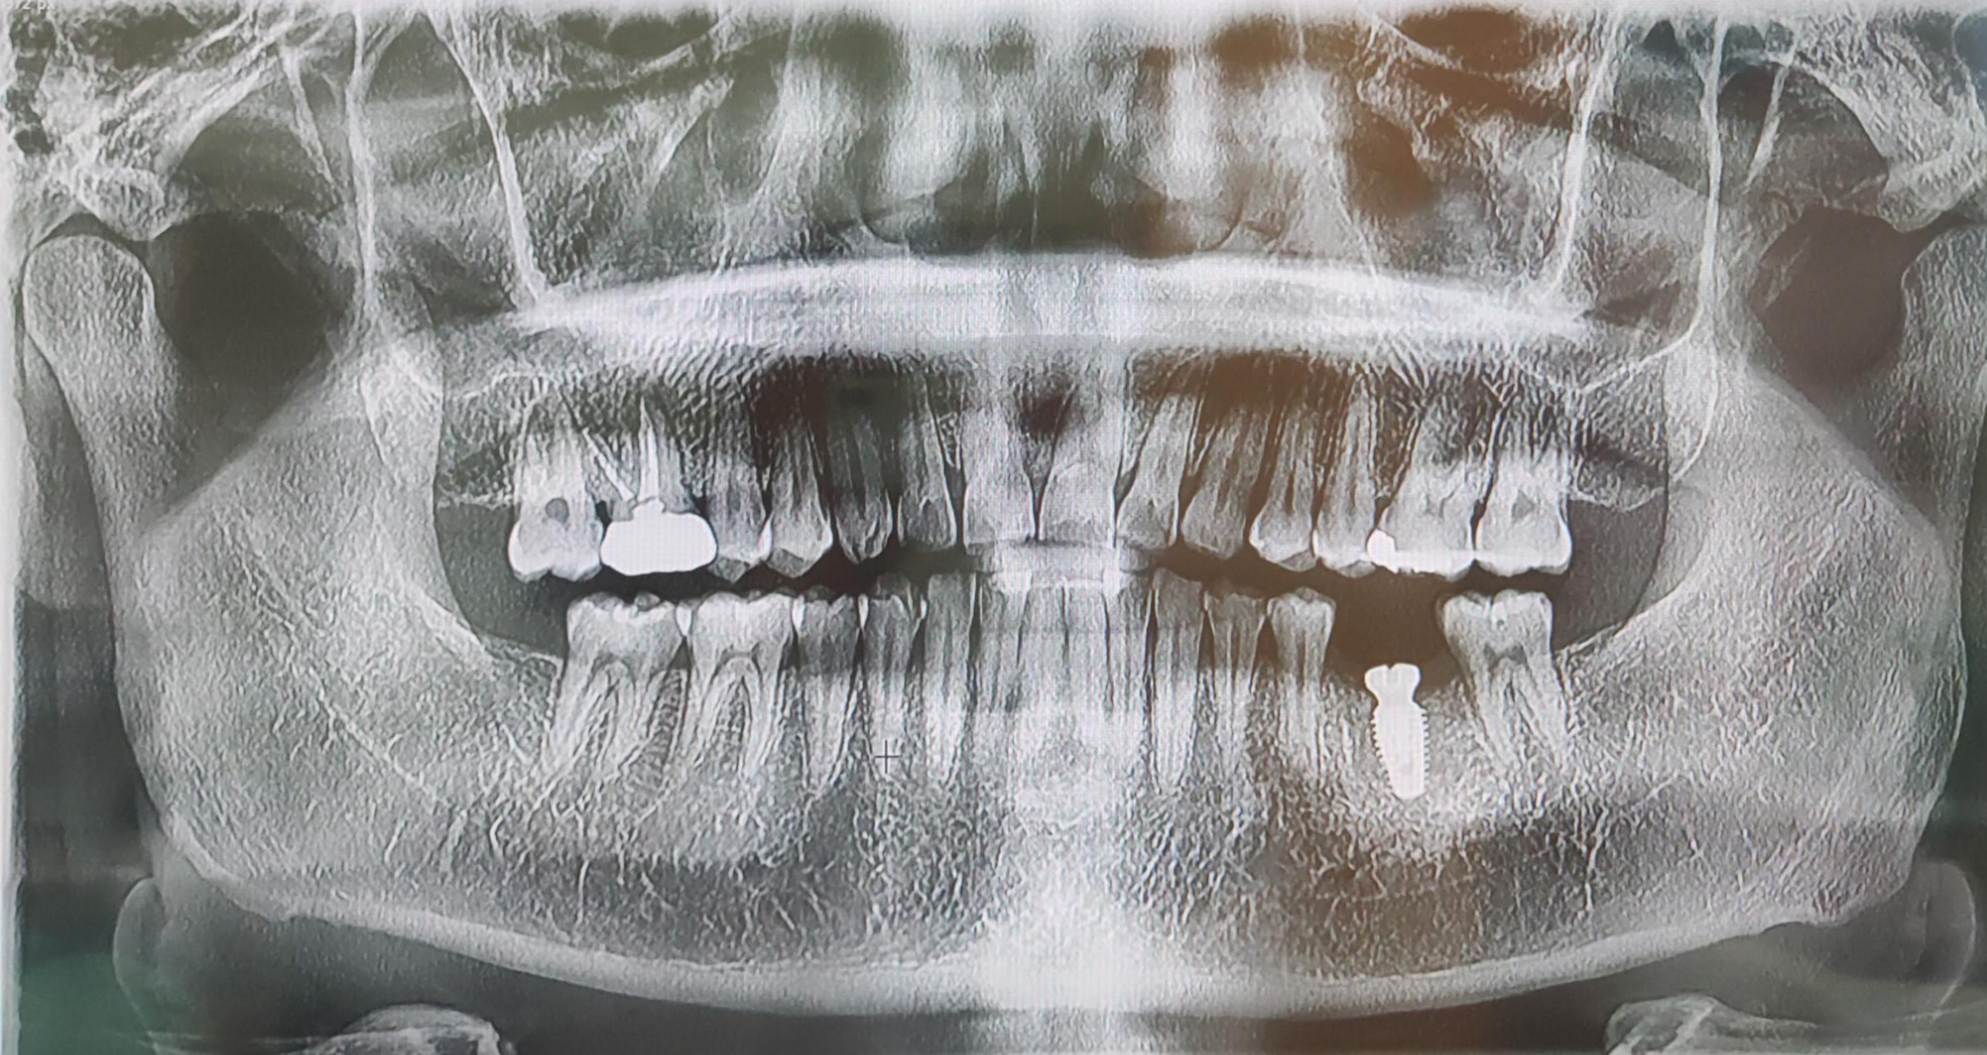

10여년 넘게 잘 사용하던 금이빨을

다시 씌운 이후에, 내부의 이빨이 치근까지 다 썩어 버려

어쩔 수 없이 임플란트를 하게 되었네요.

기둥을 세웠어요 ㅋㅋㅋ